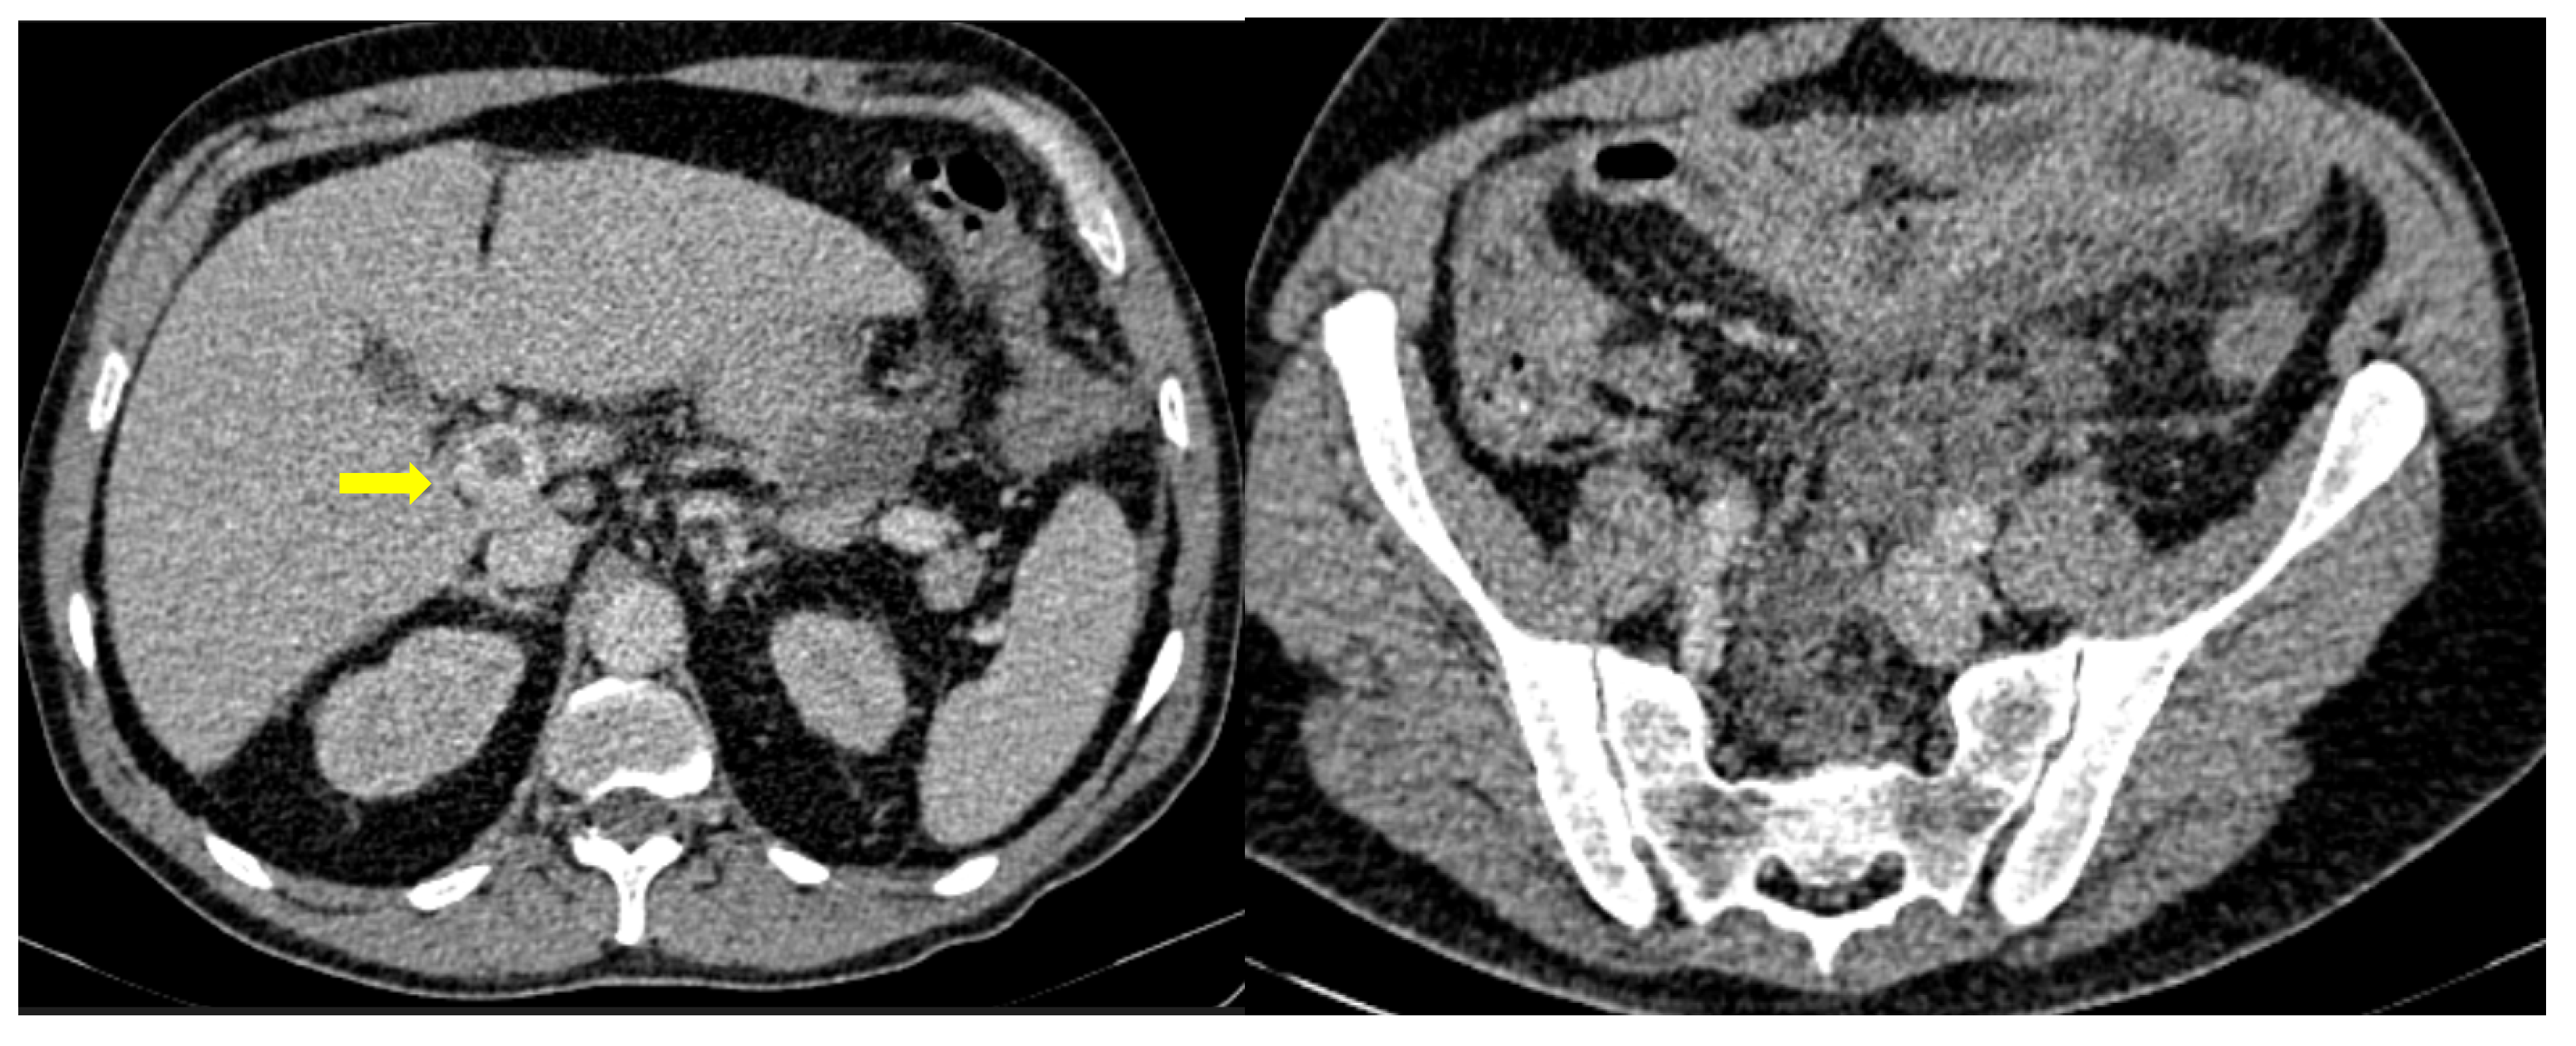

Figure 11. A 75-year-old intubated patient with COVID-19 presented with hematemesis, hypotension and acute drop of hemoglobin level. Computed Tomography revealed active intraluminal extravasation of contrast into the 2nd part of duodenum (arrow) on arterial phase (a). Further pooling of the contrast (arrowhead) is shown on portal phase (b).

GI hemorrhage is less commonly encountered in abdominal imaging, and CT findings include active intraluminal extravasation of contrast and indirect signs such as luminal distention with blood clots (Figure 11) [56].

Imaging is additionally significant to the treatment plan by identifying the exact site and extent of the bleeding as well as offering a precise and minimally invasive treatment option. Digital Subtraction Angiography can confirm the active bleeding seen as a “contrast blush”, detect the responsible branch and provide occlusion via selective embolization.